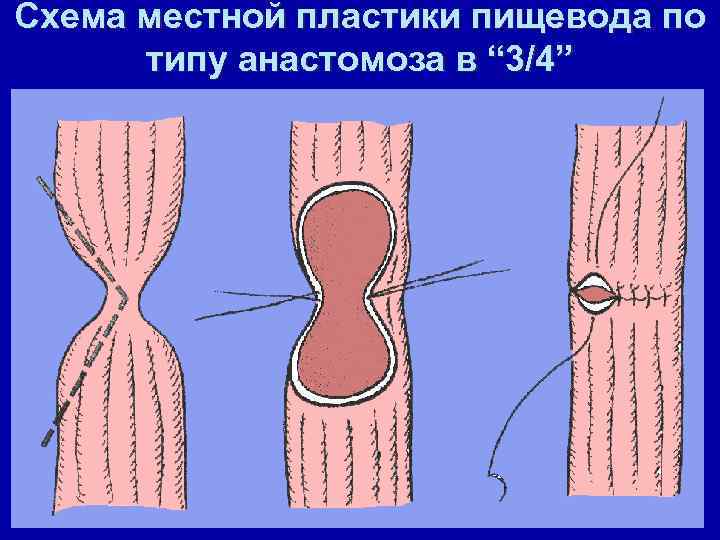

Схема местной пластики пищевода по типу анастомоза в “ 3/4”

Резекция стриктуры с наложением анастомоза "конец в конец" Схема местной пластики пищевода.

Пищеводно-пищеводный анастомоз в обход стриктуры Схема местной пластики пищевода